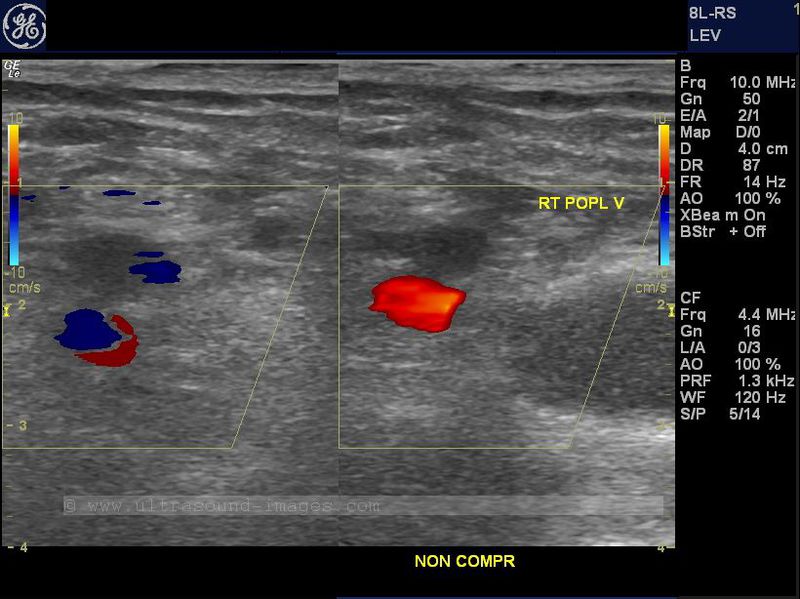

This is yet another case of right popliteal vein thrombosis in a lady complaining of pedal and leg edema. Again, the right popliteal vein shows absence of compressibility (non-compressible) despite pressure sufficient to cause deformity of the adjacent popliteal artery. In addition no flow is observed in the popliteal vein on color Doppler imaging. Further, a small cystic structure is seen medially, a Baker's cyst which is distinguished from the vessels nearby due to its oval shape and lack of Doppler signals. In addition, the right popliteal vein is dilatated at 8 mm. diameter with echogenic matter within it further confirming the presence of thrombus within it.